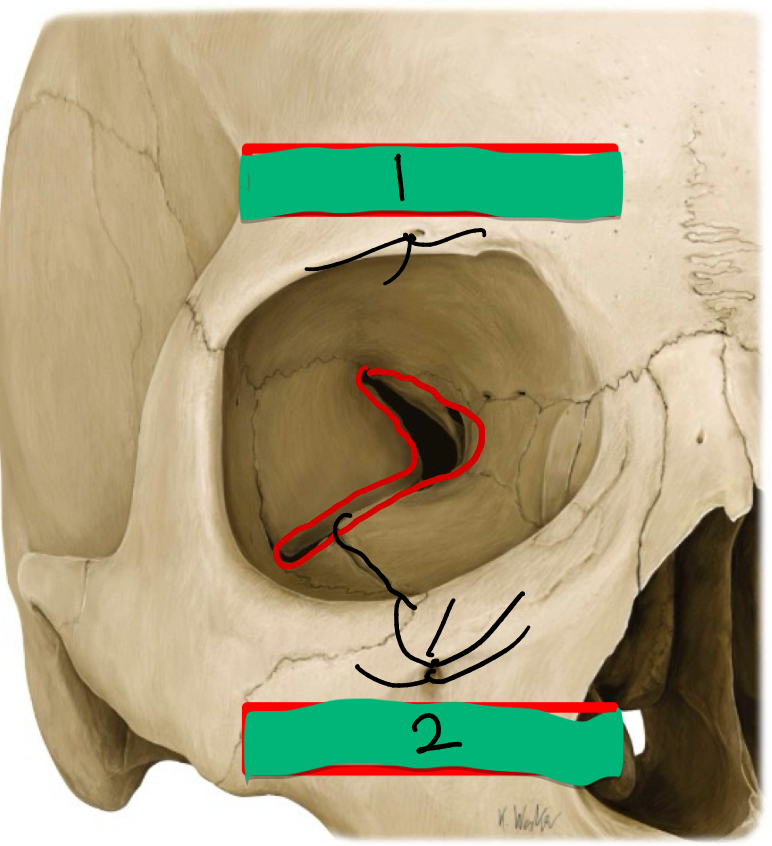

What is this and name each bone

Orbit

Frontal

Sphenoid

Zygomatic

Palatine

Ethmoid

Lacrimal

Maxilla

Fierce Zebras Sprint Past Every Lazy Monkey

What’s 1 and what nerve does it transmit?

Superior Orbital Fissure: transmits CN V1, CN III, IV, VI & Ophthalmic v

What’s 2 and what nerve does it transmit?

Inferior Orbital Fissure: transmits the Infraorbital nerve (CN V2)

What’s 3 and what nerve does it transmit?

Optic Canal: transmits Ophthalmic a. & CN II